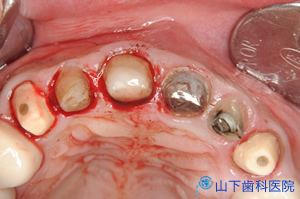

| 上顎の残っている歯すべてに金属製の内冠または沈下を抑える根面板を被せています。 | ![]() |

| 外冠が付いている「入れ歯」は味覚を落とさないよう、口蓋を中抜きした金属床です。 | ![]() |

すべての内冠の側面は、決められた主軸(取り外しの方向)から見て6度~8度内のテーパー(先細り)を持つよう精密旋盤加工します。それから個々の内冠に精密に適合する外冠を作ります。外冠の金属が眼に触れる部分は、金属色を遮蔽して白く見せる前層処理をします。外冠は内冠にピッタリはまり、簡単には外れない精度が必要です。内冠を歯に、外冠を「入れ歯」に取り付ければ、クラスプと呼ばれる留め具式の「入れ歯」より揺れが少なく、しっかり噛め、審美的にも優れた「入れ歯」になります。

このようなテーパーを付けた2重冠構造の維持装置を持つ入れ歯は、1960年代ドイツで開発され、コーヌスクローネン義歯と呼びます。ドイツ語のKonusは円錐、Kronenは冠の複数形です。この2重冠を英語圏ではGerman crownと呼んでいます。